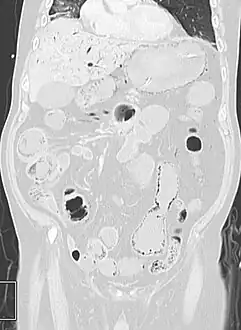

Pneumatosis intestinalis

Pneumatosis intestinalis (also called intestinal pneumatosis, pneumatosis cystoides intestinalis, pneumatosis coli, or intramural bowel gas) is pneumatosis of an intestine, that is, gas cysts in the bowel wall.[1][2] As a radiological sign it is highly suggestive for necrotizing enterocolitis. This is in contrast to gas in the intestinal lumen (which is relieved by flatulence). In newborns, pneumatosis intestinalis is considered diagnostic for necrotizing enterocolitis, and the gas is produced by bacteria in the bowel wall.[3] The pathogenesis of pneumatosis intestinalis is poorly understood and is likely multifactorial. PI itself is not a disease, but rather a clinical sign. In some cases, PI is an incidental finding, whereas in others, it portends a life-threatening intra-abdominal condition.